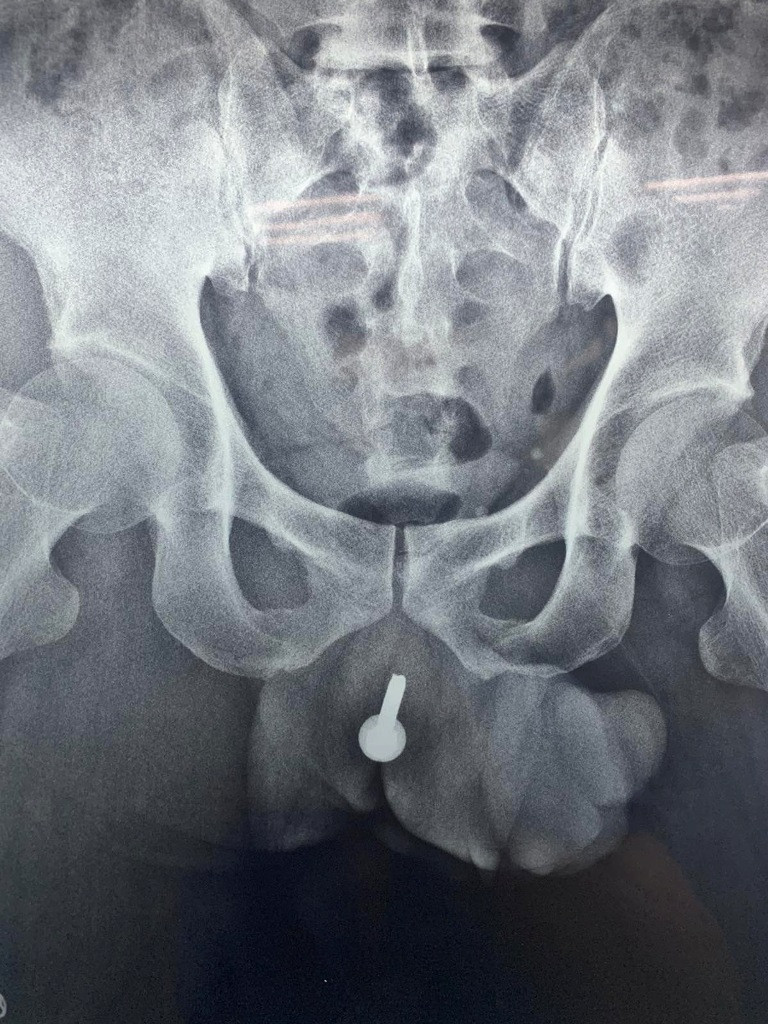

Anh T. nhanh chóng được ê kíp trực cấp cứu thực hiện các xét nghiệm, siêu âm, X-quang. Kết quả ghi nhận một dị vật dài khoảng 6cm nằm dọc theo niệu đạo. Dị vật khiến bệnh nhân vô cùng đau đớn, không đi tiểu được, không thể ngủ được và có nguy cơ nhiễm khuẩn, gây áp xe vùng niệu đạo sinh dục. Ngay lập tức, người bệnh được mổ cấp cứu chuyển lưu nước tiểu bằng phương pháp mở bàng quang ra da, giúp hạn chế tối đa nguy cơ nhiễm khuẩn.

Hình X-quang thấy dị vật nằm sâu trong niệu đạo (ảnh: BVCC) Sau khi hội chẩn với các bác sĩ Đơn vị Niệu đạo, người bệnh được tiếp tục thực hiện nội soi niệu chẩn đoán. Nhận định ban đầu trong quá trình nội soi, dị vật được xác định là một chiếc ốc vít thường dùng trong xây dựng. Kết quả nội soi ghi nhận niệu đạo viêm nhiều, xung huyết, có dấu hiệu nhiễm trùng. Người bệnh được lên lịch phẫu thuật bán khẩn lấy dị vật.